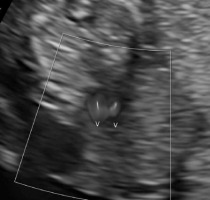

Moreover, the fetal heart seemed to possess four cavities, two slightly asymmetrical inflows of the ventricles and the origins of two vessels in abnormal relationships were visualized (Figures 4-5).